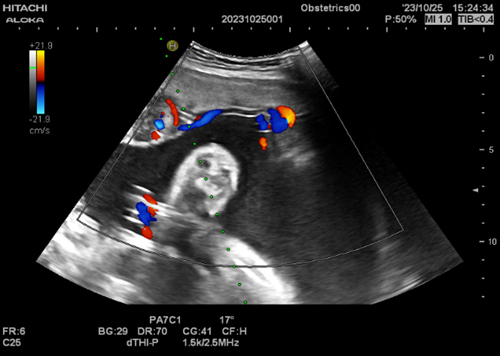

胎盘绒毛膜血管瘤

射频消融术前供血血流情况